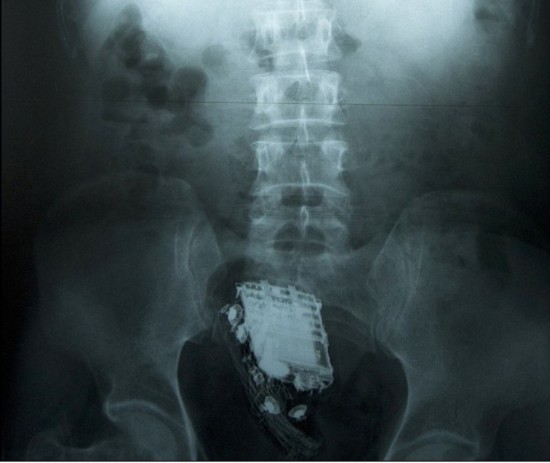

X射线扫描显示,手机被深深地塞进了直肠里。

这名58岁的男子因偷盗罪被判处10年监禁,目前正在斯里兰卡首都科伦坡的韦利卡达监狱服刑。为了能把手机顺利取出,狱警后来把他送进了医院。X射线扫描显示,手机被深深地塞进了直肠里。